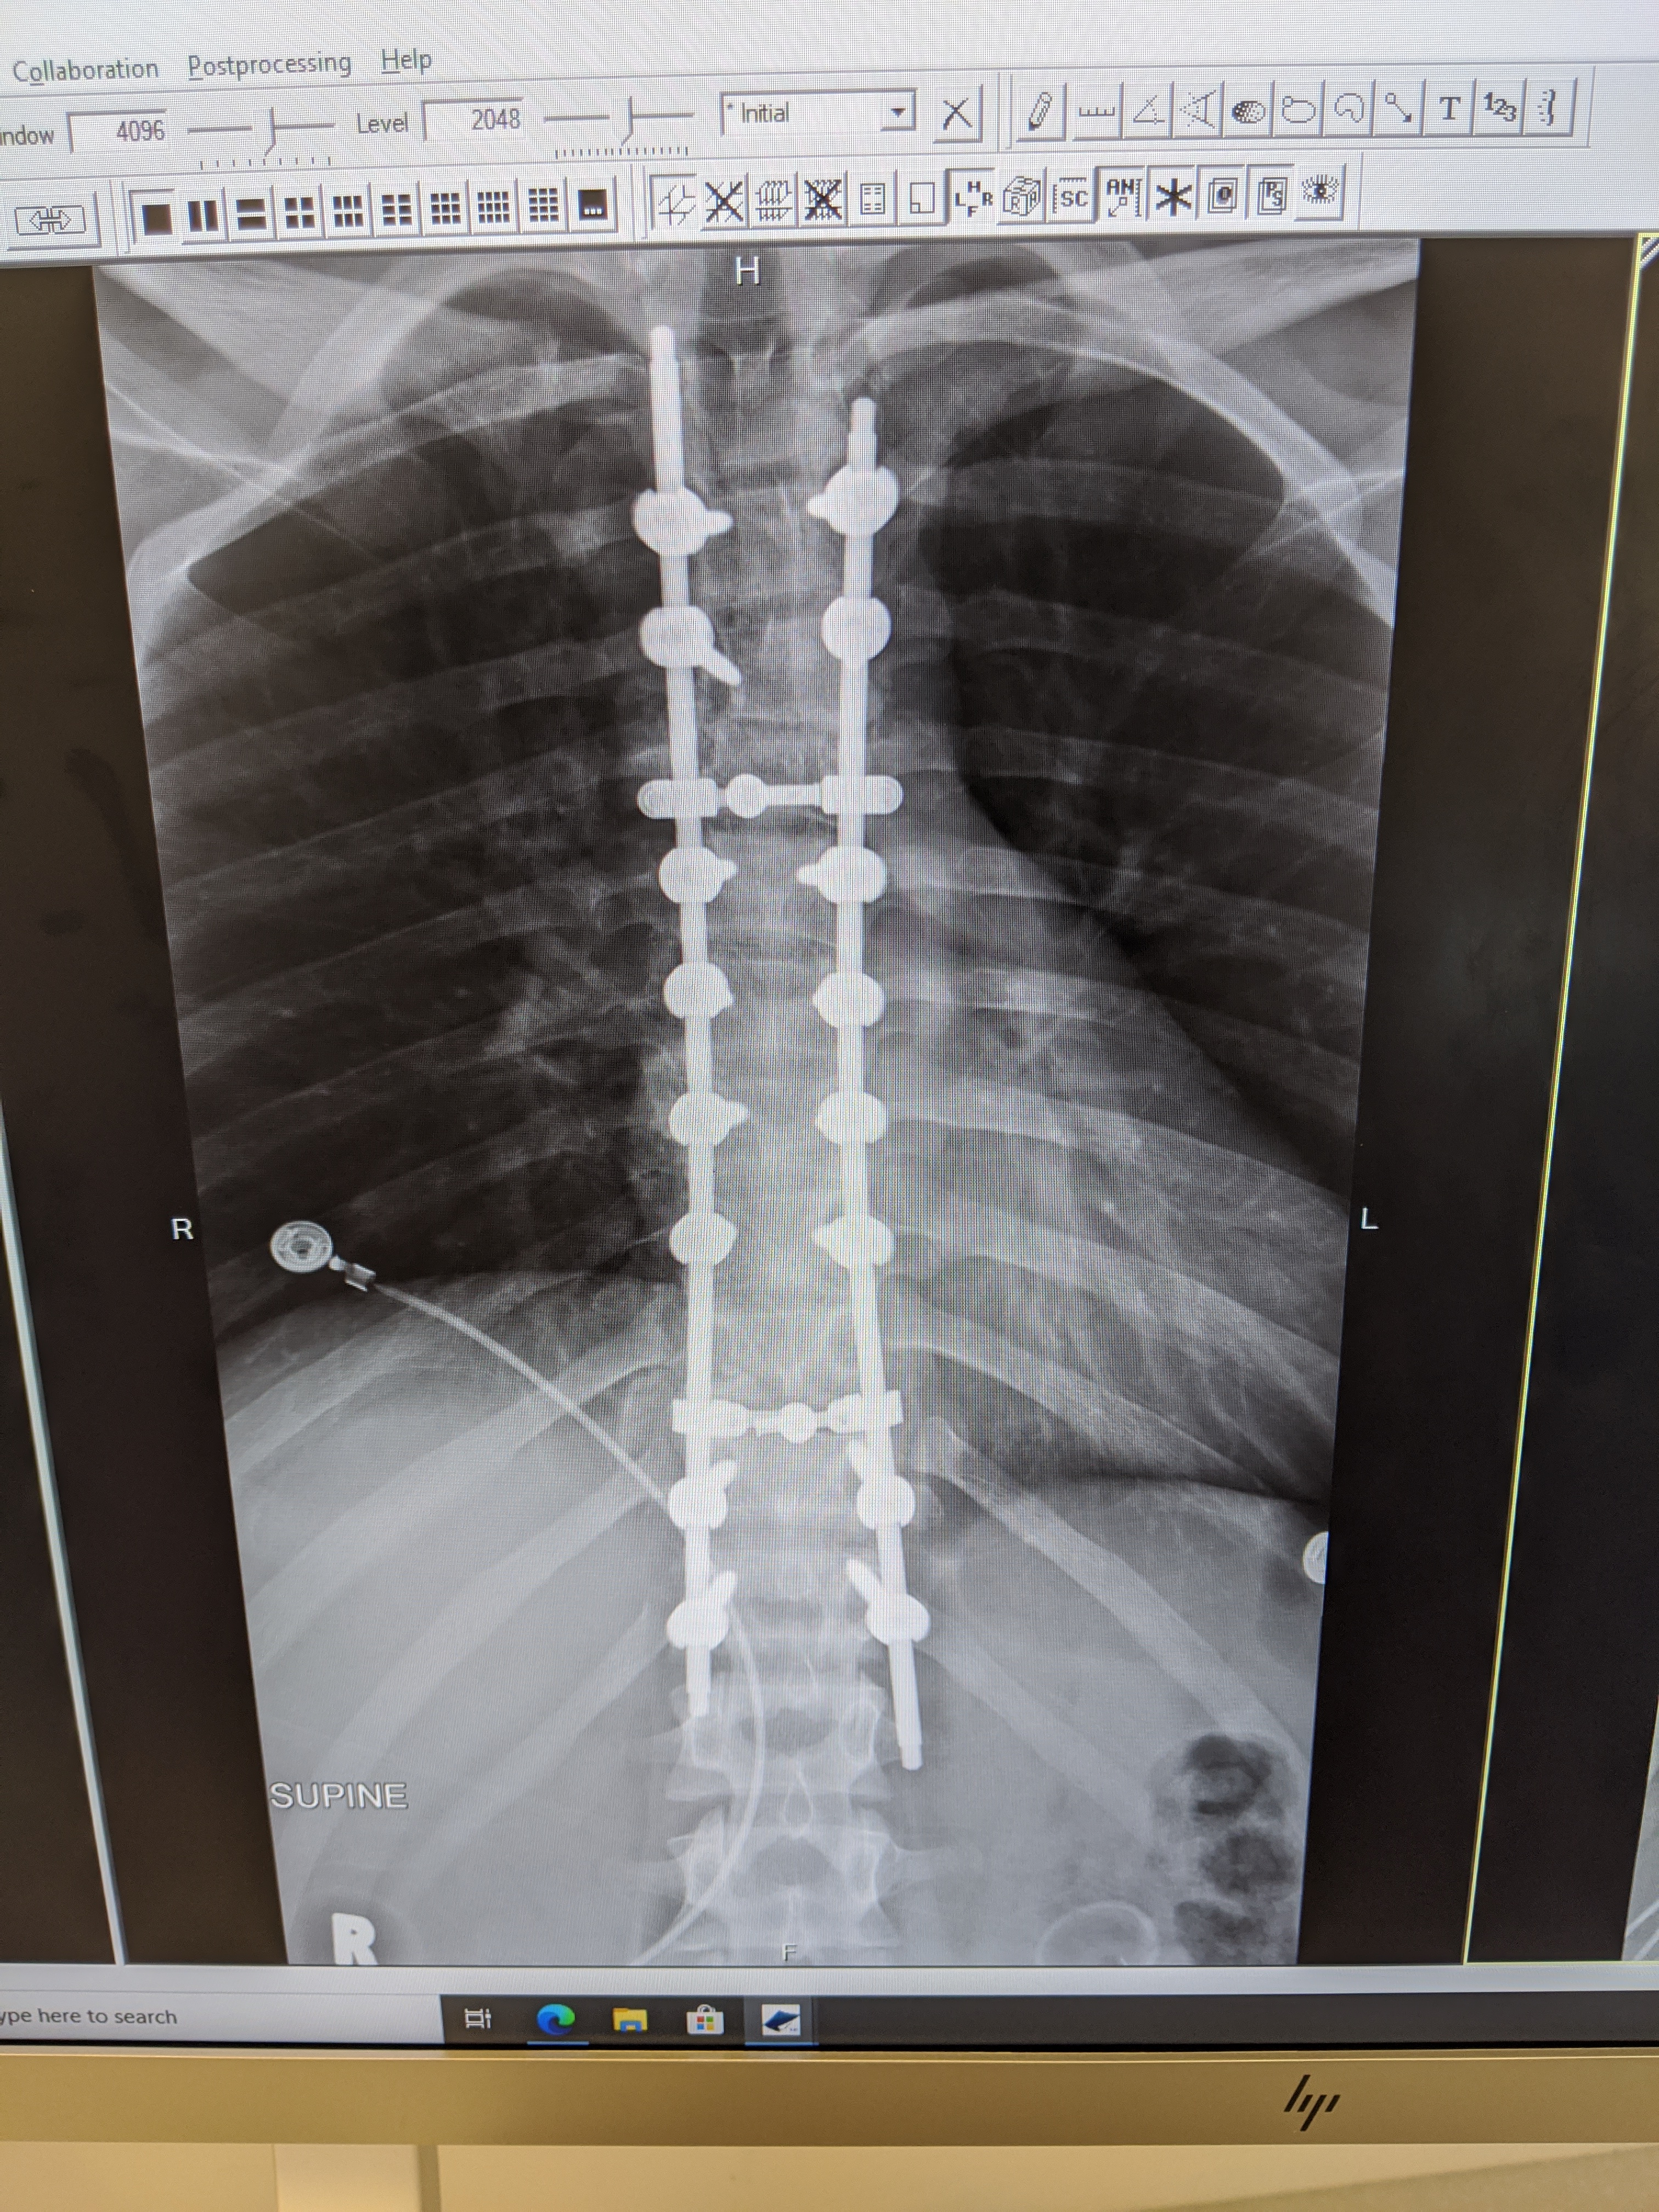

On May 19, 2020, Elijah Powell was a passenger in a serious car accident.

As a result, Elijah suffered a severe spinal cord injury as well as a significant brain injury, collapsed lung, fractured wrist. After over a month in ICU at the University of Maryland Shock Trauma Center in Baltimore, Elijah will transfer to Mt. Washington Pediatric Hospital for intensive inpatient rehabilitation. He has made significant improvement, but will require a great deal of support moving forward.